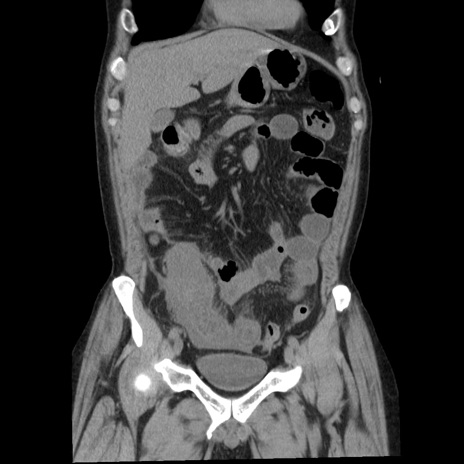

症例29(冠状断像)

【症例】40歳代男性

【現病歴】2日前から胃痛あり。徐々に周期的な激痛に変化した。本日になっても激痛があるため受診。

【身体所見】意識清明、BT 38-39℃台あり、腹部:膨満、やや硬、右下腹部に圧痛あり。

【データ】WBC 8500、CRP 23.26